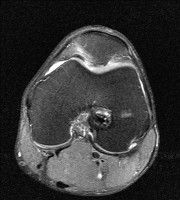

무릎 mri 간단히 봐주실 수 있으시나요 ㅠㅠ

안녕하세요 8년전 십자인대 수술하고 최근 무리한 운동에 무릎 불편감이 생겨서

mri 찍었습니다.

진단결과는 첫 찍은 병원에서 활액막염 이라는 진단을 받았습니다. 혹시 봐주실 수 있으실까요?

올라온 MRI가 단편적이라서 정확한 진단에 어려움이 있지만 십자인대에는 큰 이상이 있지는 않은것 같으며, 무릎관절내 물이 있는 것으로 보아 활액막염의 진단이 맞을 것 같습니다.

하지만 단편적인 영상이기 때문에 촬영병원에서 정확한 판독지 등을 받으시는 것이 좋겠습니다.